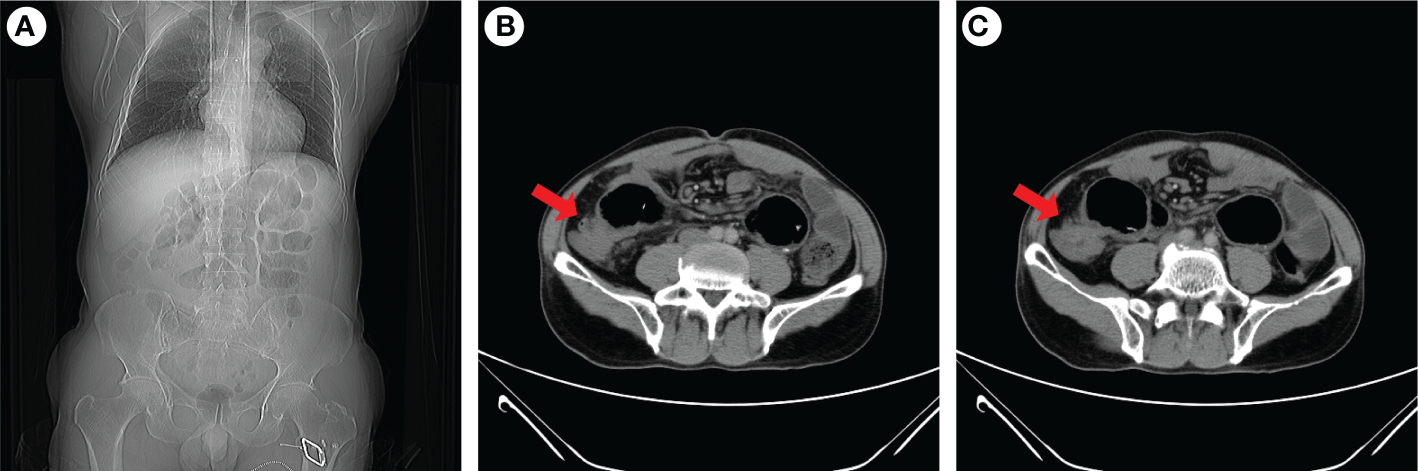

Figure 3

Abdominal CT examination of the patient when intestinal obstruction occurs again. Coronal images indicated gas and fluid accumulation in the intestine (A), and transverse images revealed ileocecal intestinal wall thickening (B, C). The red arrow indicaes the ileocecal junction.